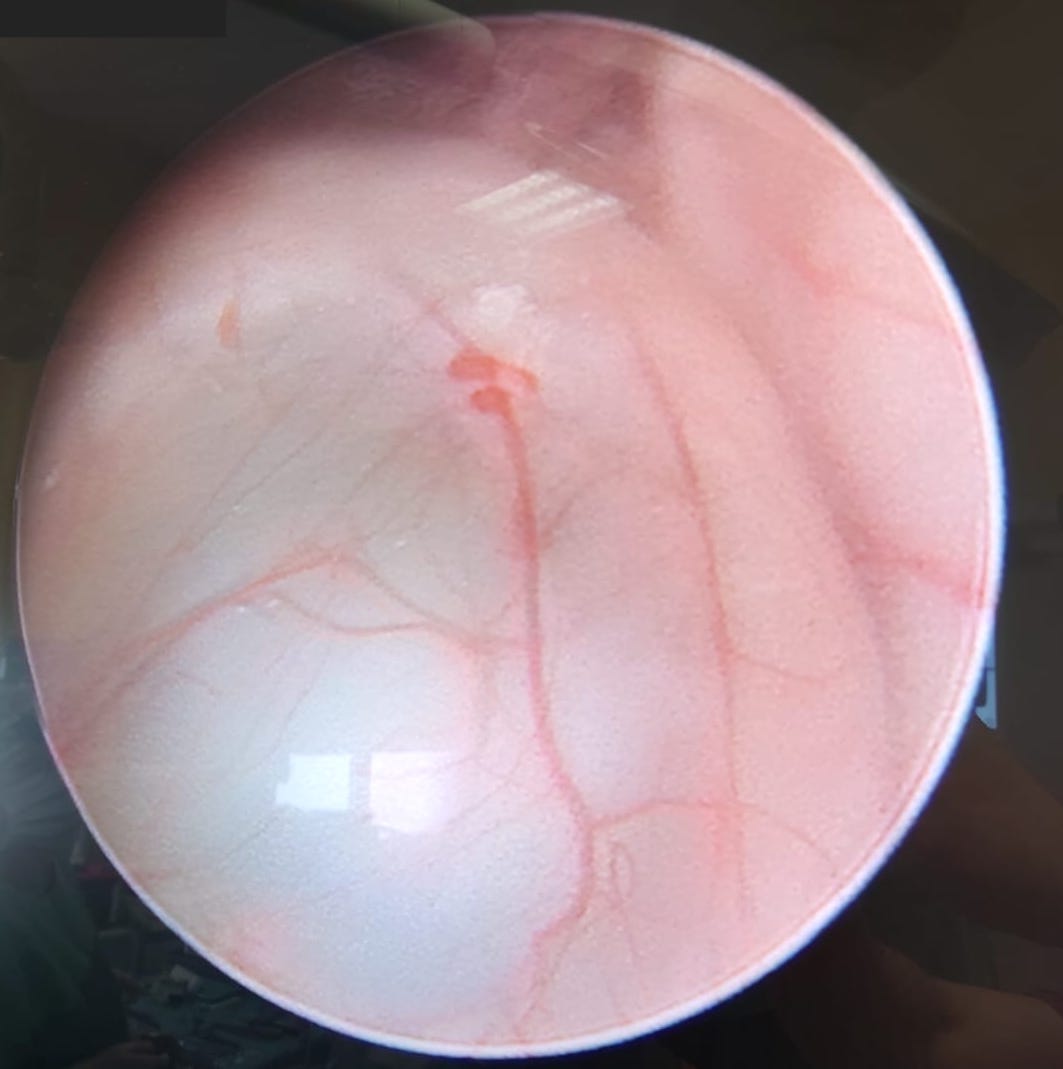

Pathologies of the pineal gland region are frequently encountered in daily neurosurgical practice. It is important to remember that, besides usually asymptomatic pineal gland cysts, neoplasms of a different origin may also occur in this region. The rarity of the most dangerous lesions – pineal gland apoplexy and pineal tumors – might cause problems with proper diagnosis and treatment. Their occurrence is commonly associated with symptomatic hydrocephalus caused by aqueductal stenosis. Currently, in such cases, endoscopic procedures, including endoscopic third ventriculostomy (ETV), are commonly and widely chosen as treatment options. Endoscopic procedures not only enable decompression of hydrocephalus but also further diagnosis of its cause. Herein, we present 3 case reports of endoscopic treatment with ETV performed in patients with hydrocephalus related to pineal region pathologies.